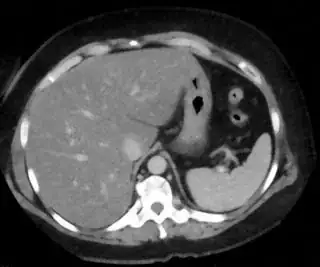

My problem is when I change image , rgb value of liver section may be different. Here is other sample image

Sample image 2.

For this image rgb value vary from 160 to 190 for each color component (r, g & b). Please help me to solve the problem.